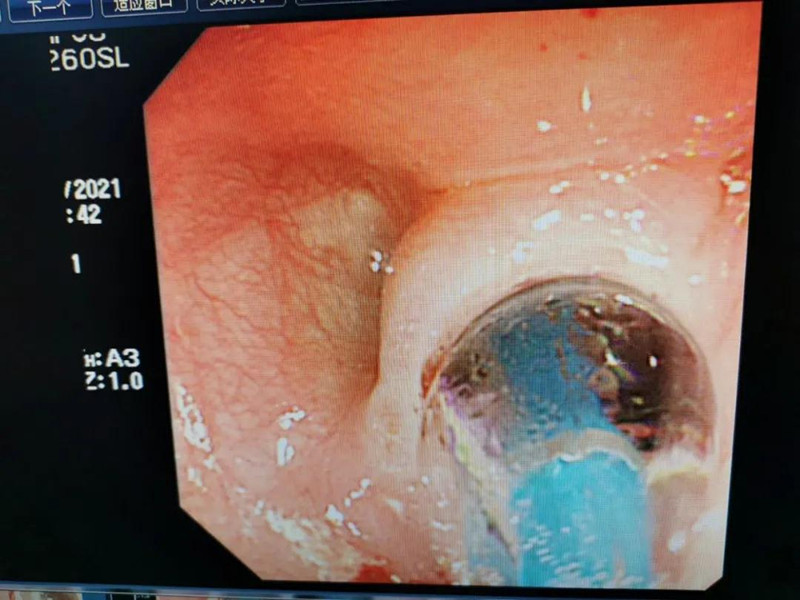

天天6个月了。最近总出现呛奶的情况,后来还出现肺炎症状。在啪啪网 经食道造影后,医生发现天天的症状是由术后并发症“食道吻合口狭窄”引起的,最窄处仅5mm多一点。食道狭窄球囊扩张术是目前最适合天天的手术了。内镜中心副主任边鹏说,这是一种微创介入治疗,具有创伤小、恢复快、合并症少的优势。2月26日,在麻醉科、内镜中心团队的合作下,边鹏为天天行经内镜下食道狭窄球囊扩张术。术中,边鹏用直径8mm的球囊进行扩张,将原来狭窄的食道扩成直径8mm的宽度。

天天太小,在球囊扩张的过程中,需要格外注意,不能扩张太快,否则会出现穿孔或大出血。所以边鹏每扩张3分钟,暂停3分钟,共扩张了3次。整个扩张过程很顺利,效果也非常好。次日,天天就出院了。在球囊扩张前,小儿内镜下显示,天天食道吻合口狭窄处上端竟有一团纸,家长也不清楚孩子是什么时候吃了纸。因为吻合口处太窄,纸下不去,形成了阻隔,导致天天最近总呛奶,奶汁进入气道,最终出现肺炎。